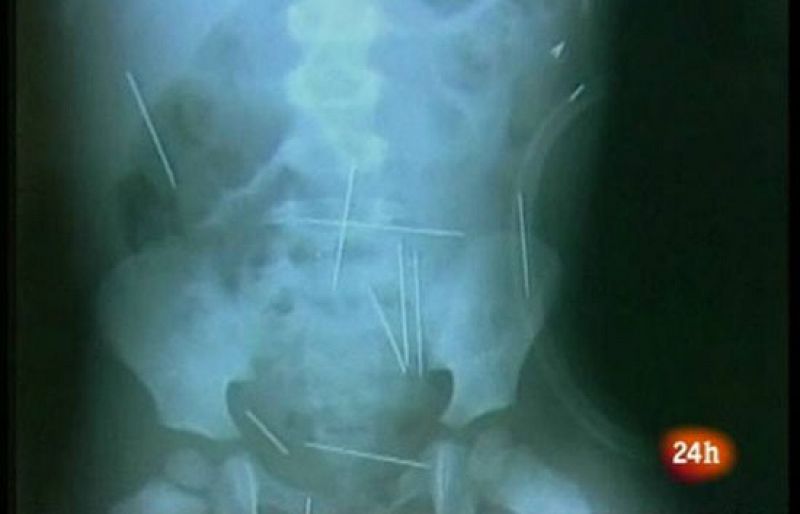

El brasileño que le incrustó decenas de agujas de coser a su hijastro de dos años de edad ha confesado a un canal de televisión que antes de clavarlas en su cuerpo dormía al pequeño con vino y ha reiterado que lo hacía todo para vengarse de su esposa.

"Fue una idea muy loca", apunta el agresor, quien ha confesado que le clavó las agujas al niño "dos o tres veces por semana" durante un mes con la intención de "matarlo" y "golpear" así a la madre, con la que dijo que "peleaba todo el tiempo, todos los días".

Hasta ahora, los responsables por la atención del pequeño no han podido determinar cuántas agujas le fueron clavadas.

Inicialmente se habló de unas 50, luego de 42 y ahora se cree que fueron 31, por lo que aún tendría, por lo menos, 27 agujas dentro de su cuerpo.